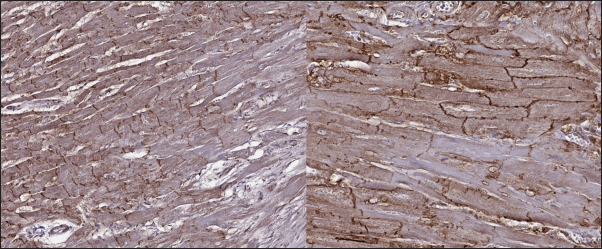

In the myocardial samples of healthy cats, we did not find any significant structural alterations. The cardiomyocytes were presented as cell stripes with one or two centrally located nuclei, Z disks were easily recognized, and striation was presented. The interstitial spaces were not expanded, and the capillary lumen was noticed. Masson’s trichrome staining for fibrosis did not reveal a significant increase in collagen fibers, with sporadic fibers observed in interstitial spaces and near vessels (Fig. 3). Immunohistochemical staining for Cx43 revealed the typical distribution of proteins accumulated in cell-to-cell connections via intercalated disks. Weak-to-absent signals were observed in the lateral wall of the cardiomyocytes. The immunoadsorption zone exhibited a solid line without disruptions or lesions (Fig. 4).

Fig. 4. Immunohistochemistry. Normal myocardium of the cat. Cx43 proteins located in zones of cell-to-cell contact. Stained with Cx43 antibodies.